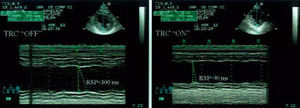

- Retraso septo-pared posterior (RSP). El retraso (diferencia en ms) entre la excursión máxima del septo y la pared posterior, medidas en modo M y en el eje corto parasternal.

Respecto a las mediciones basales, la estimulación biventricular disminuyó de forma significativa el RSP (fig. 2) en el grupo global de pacientes a los 3 meses con el dispositivo conectado (218,3 ± 44,7 frente a 86,6 ± 35,4 ms; p < 0,001). No hubo diferencias entre el RSP basal y a los 3 meses con el dispositivo desconectado (218,3 ± 44,7 frente a 211,6 ± 34,7 ms; p = 0,56).

Fig. 2. Imágenes ecocardiográficas modo M en el eje corto paraesternal, donde se observa la disminución en el retraso entre el septo y la pared posterior con el marcapasos conectado (imagen derecha) en relación con el marcapasos desconectado (imagen izquierda). RSP: retraso septo-pared posterior; TRC «off»: sin terapia de resincronización cardíaca; TRC «on»: con terapia de resincronización cardíaca.